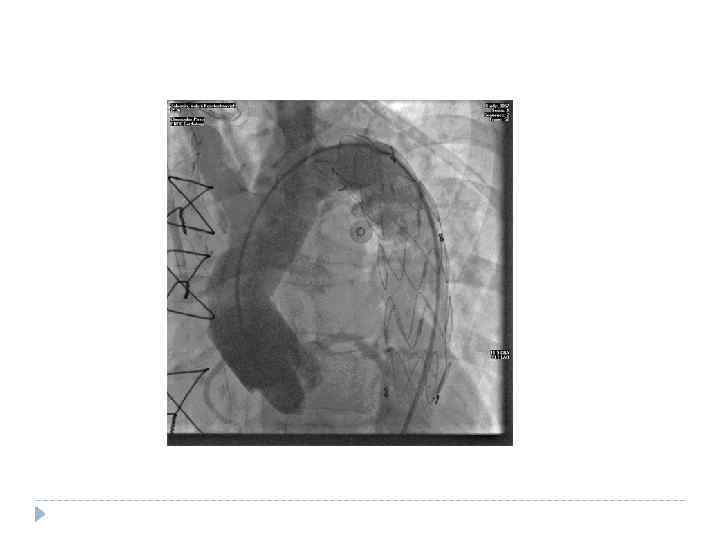

Систолический шум Почти у половины больных с рассливающей аневризмой аорты отмечаются признаки аортальной недостаточности - диастолический шум и снижение уровня диастолического артериального давления. Исключение ишемии по ЭКГ RG, КТ, тотальная аортография

Систолический шум Почти у половины больных с рассливающей аневризмой аорты отмечаются признаки аортальной недостаточности - диастолический шум и снижение уровня диастолического артериального давления. Исключение ишемии по ЭКГ RG, КТ, тотальная аортография

Аневризма восходящего отдела аорты Иногда достигает таких больших размеров, что пульсация ее становится ощутимой или даже видимой во втором или первом межреберье у края грудины.

Аневризма восходящего отдела аорты Иногда достигает таких больших размеров, что пульсация ее становится ощутимой или даже видимой во втором или первом межреберье у края грудины.

Иногда она сдавливает правый бронх, вызывая кашель, одышку. Эрозия стенок бронха или трахеи может сопровождаться небольшим кровотечением. В редких случаях сдавливается верхняя полая вена с развитием характерной сети расширенных подкожных вен на передней стенке грудной клетки. Эрозия ребер и грудины приводит к появлению сильных болей в груди. Аневризма восходящей аорты чаще всего оказывается сифилитической (встречаются так же атеросклеротическая и идиопатическая).

Иногда она сдавливает правый бронх, вызывая кашель, одышку. Эрозия стенок бронха или трахеи может сопровождаться небольшим кровотечением. В редких случаях сдавливается верхняя полая вена с развитием характерной сети расширенных подкожных вен на передней стенке грудной клетки. Эрозия ребер и грудины приводит к появлению сильных болей в груди. Аневризма восходящей аорты чаще всего оказывается сифилитической (встречаются так же атеросклеротическая и идиопатическая).